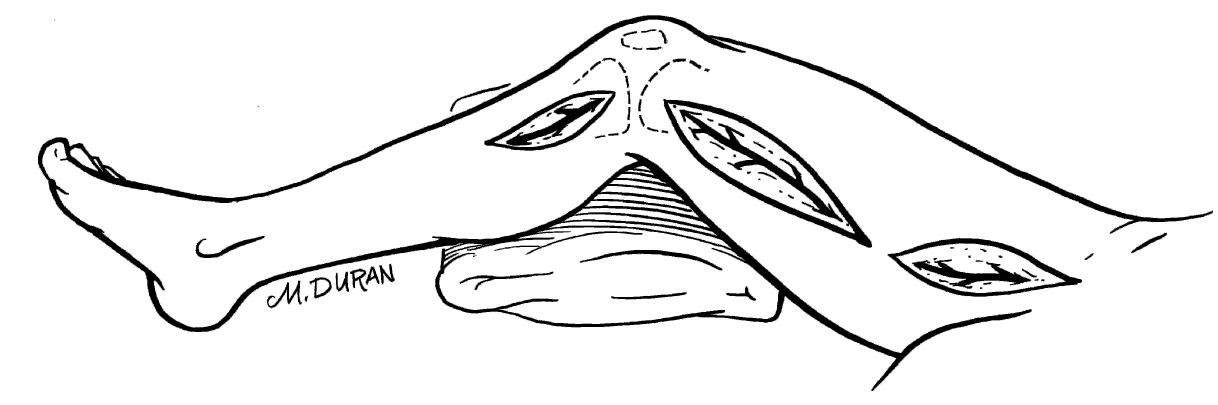

The paper discusses the surgical anatomy and techniques associated with various procedures, with particular emphasis on the anatomy of the scalp, including its vascular, lymphatic, and nerve supplies. It presents detailed insights into the blood supply of the scalp, highlighting the important arterial branches and their anastomoses, as well as the implications for surgical procedures. Additionally, the paper outlines techniques for surgical interventions, positioning, and considerations necessary for effective outcomes.